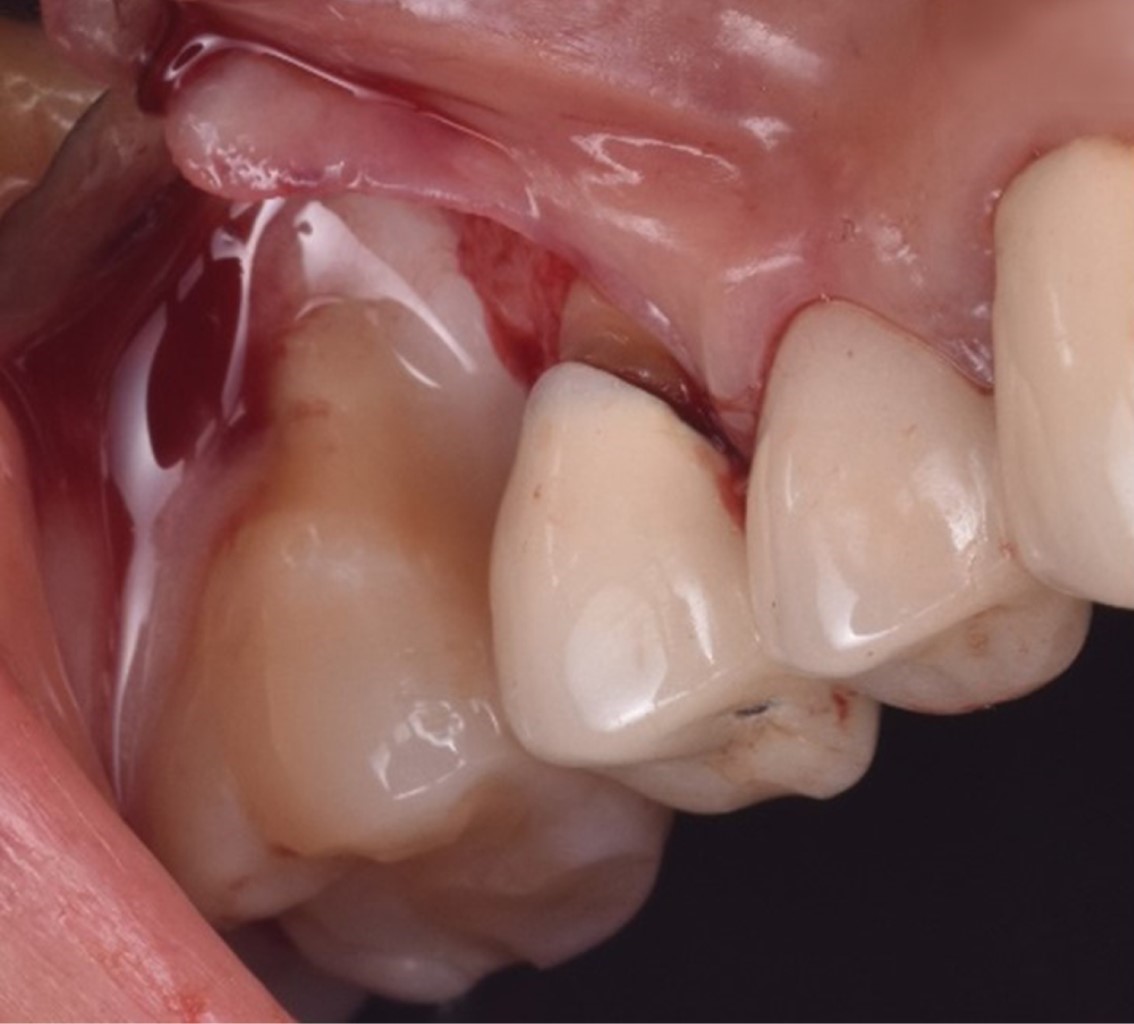

Las proteínas derivadas del esmalte (Emdogain®) se obtienen por medio de la odontogénesis en el periodo de yema de la dentadura porcina; la proteína principal es la amelogenina que presenta una biocompatibilidad con las proteínas del esmalte humano. Los cultivos in vitro han demostrado que Emdogain® al ser agregado a los fibroblastos causa una mejora en la producción de proteínas y colágeno, mineralización y proporciona condiciones favorables a la matriz, proliferación celular, migración, diferenciación y síntesis (Figuras 1, 2, 3, 4, 5 y 6). La capacidad osteogénica se relaciona de manera directa con las proteínas que contiene y esto produce una capacidad osteoinductiva y puede contener factor de crecimiento transformante beta y proteína morfogénica ósea (BMP, por sus siglas en inglés) aunque en menor cantidad.10

Se presenta, en la Especialidad en Periodoncia de la Universidad Autónoma de Baja California (UABC) campus Mexicali, un paciente femenino de 60 años, ASA I, sin antecedentes patológicos, cuyo motivo de consulta es "tengo una bolsa periodontal desde los ocho años". Se realizó una evaluación extraoral en la que se detectó hipertrofia bilateral del músculo masetero, de manera intraoral se observó un fenotipo delgado, presencia de restauraciones desajustadas, desgaste por bruxismo en bordes incisales y cúspides. En el análisis clínico-radiográfico se obtuvo una profundidad de sondaje de 12 mm, efecto intraóseo de una pared según la clasificación de Goldman & Cohen (Figura 7) por vestibular del segundo molar superior derecho, movilidad grado II, con presencia de sangrado, sin sensibilidad. Radiográficamente se observó una zona radiolúcida adyacente a la raíz mesial del segundo molar superior derecho sin presencia de lesión periapical (Figura 8) y, por lo tanto, se estableció el diagnóstico según la "Clasificación de Condiciones y Enfermedades Periodontales y Periimplantarias 2017" como: salud gingival y periodontal en un periodonto reducido, paciente no periodontal, asociado a un trauma oclusal primario;11 y como factor de riesgo se tiene el antecedente de la pérdida prematura del primer molar superior derecho y la mesialización del segundo molar superior derecho.

Figura 1

Figura 2

Figura 3

Figura 4

Figura 5

Figura 6